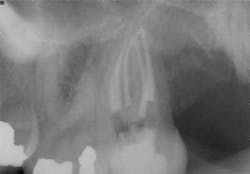

These are important questions that deserve more attention, because this canal can be difficult to locate and difficult to negotiate to the apex. By my way of thinking and practicing, every maxillary molar tooth has at least four canals. (Figure 7) This mindset helps me stay focused and determined to locate all of the canals. Some mesial-lingual canals are located at the level of the pulp chamber directly lingual to the mesial-buccal canal, and these canals are going to be more easily located than the ones that are 1 mm or 2 mm apical to the pulpal floor and significantly more mesial than the mesial buccal. Bottom line: The mesial-lingual canal orifice is variable in its lingual extent and in both the mesial-distal and coronal-apical position, but it is present with such a high frequency that a thorough exploration of the area, aided by enhanced magnification and illumination, should yield positive results in 90% of maxillary first molars and a slightly lower percentage in maxillary second molars. (20) In my experience, the closer the two canals are at the chamber level, the more likely they are to join. Again, there are exceptions to this and every rule, but these exceptions comprise a very small percentage of cases.

mesial buccal root of maxillary first molars. This tooth initially

had three distinct canals in the mesial buccal root. Following

final shaping, two canals joined at various levels, but the third

canal had no connection.

buccal canals. The two canals were very close in the chamber,

but branched in the apical portion of the root to exit via

distinct openings.

of the maxillary molar: four canals total with the two canals in

the mesial buccal root joining to exit a common foramen.